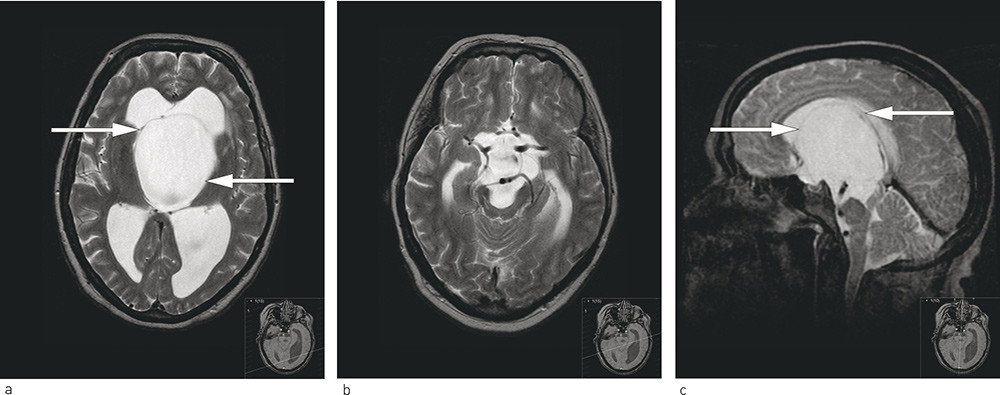

Videre utredning med MR caput viste obstruktiv hydrocephalus som så ut til å være forårsaket av en suprasellær, prepontin cyste. Cysten var sannsynligvis en araknoidalcyste (fig1a – c), og obstruerte tredje ventrikkel og utløpet til aqueductus Sylvii. Pasienten ble henvist til regionsykehus, der diagnosen araknoidalcyste ble verifisert, og samme år ble han operert med forsøk på å fenestrere cysten endoskopisk. Cysteveggen lot seg imidlertid ikke penetrere, men cysten ble likevel krympet ved bruk av diatermi. Ny MR-undersøkelse et par måneder senere bekreftet at araknoidalcysten hadde krympet noe, og ved samtidig klinisk kontroll på regionsykehus var gangfunksjonen bedret. Man sa seg derfor fornøyd og anbefalte oppfølging på lokalsykehus. Kopi av det polikliniske notatet fra regionsykehuset ble imidlertid kun sendt til fastlegen, og pasienten ble aldri kontrollert ved lokalsykehuset.